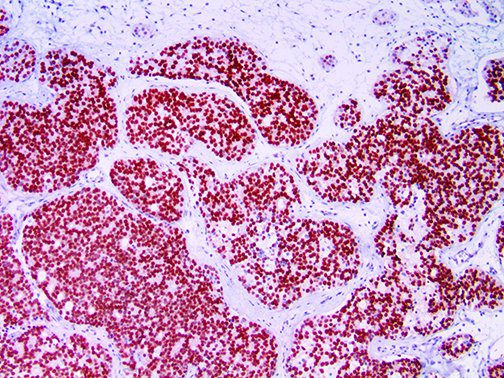

It is the ICU physician who is most likely to witness one of the deadliest manifestations of the abnormal immunological response, the cytokine storm syndrome (CSS). This response is also referred to by some as the cytokine release syndrome (CRS). CSS is characterized by continuous activation and expansion of macrophage and lymphocyte populations, which secrete large amounts of cytokines, causing the cytokine storm. This massive cytokine release is akin to hemophagocytic lymphohistiocytosis (HLH) disease, a syndrome characterized by initial unchecked and persistent activation of cytotoxic T lymphocytes and NK cells.

Clinical and laboratory manifestations of HLH include fever, enlarged liver and/or spleen, neurologic dysfunction, coagulopathy, liver dysfunction, cytopenias (i.e., low levels of erythrocytes, leukocytes, and/or platelets), hypertriglyceridemia, hyperferritinemia, hemophagocytosis, and eventually diminished NK cell activity as the immune system becomes progressively paralyzed. HLH can be familial (primary HLH) or secondary to another disease process (sHLH), such as rheumatic disease, in which it is referred to as macrophage activation syndrome (MAS, characterized by elevated ferritin).